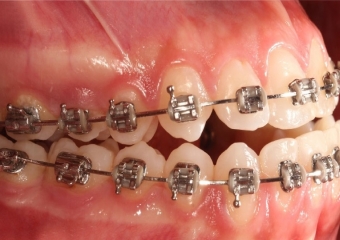

Oclusão após a cirurgia